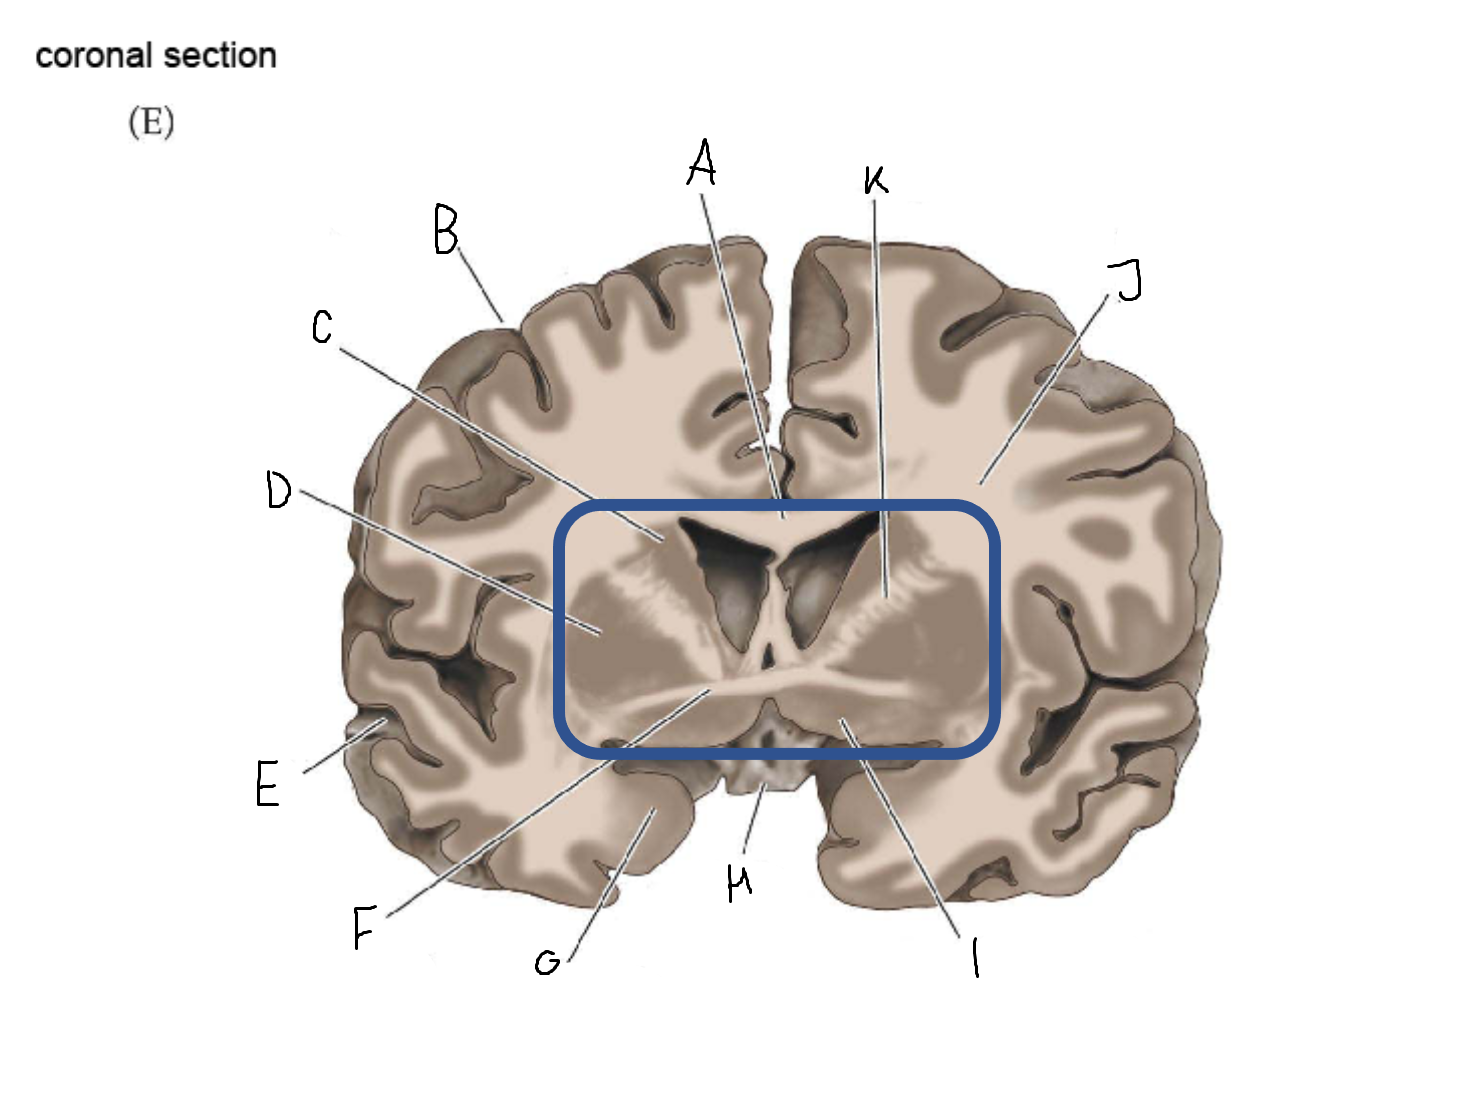

A

head of caudate nucleus

C

putamen

D

external segment of globus pallidus

E

internal segment of globus pallidus

F

third ventricle

G

thalamus